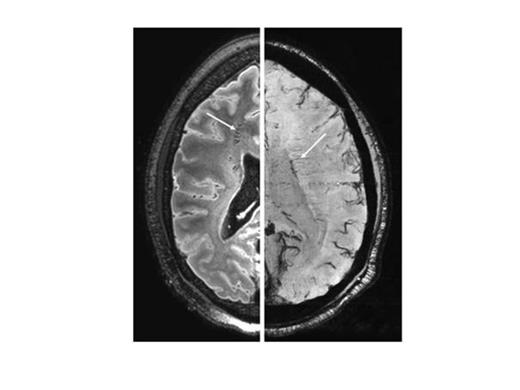

With the exception of two patients, all displayed round and circumscript infarcts in the deep white matter of the frontal or parietal lobe (Table). Most lesions (82%) were <5 mm. In one patient (A) we identified 164 white matter infarcts (Figure 1). Strikingly, one patient (patient B) had several cortical micro-infarcts (Figure 2) although she had no neurological symptoms. These were associated with an occluded A1 and A2 segment of the anterior cerebral artery. In addition, this patient had unique pattern of white matter lesions, consisting of irregular shaped white matter infarcts, some located periventricular, and others close to the cortical infarcts. In two other patients (patients C and D) we identified an isolated cortical micro-infarct despite the absence of large vessel vasculopathy. In patient C, we found numerous hypo-intense areas symmetrically distributed in the deep white matter of the frontal and parietal lobe (Figure 3). These areas were associated with prominent transmedullary veins.

7T MP-FLAIR image (left) with hypo-intense structures (arrow) in patient C, and 7T dual-echo T2*-weighted scan (right) with prominent transmedullary veins (arrow).